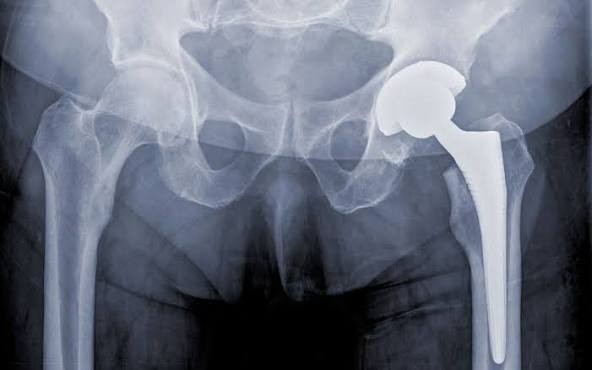

- Materials: Components are made from metal, ceramic, and plastic.

- Fixation: Implants may be cemented or press-fit, allowing bone to grow into a porous coating.

- Lifespan: Modern hip implants often last 15–25 years or longer.